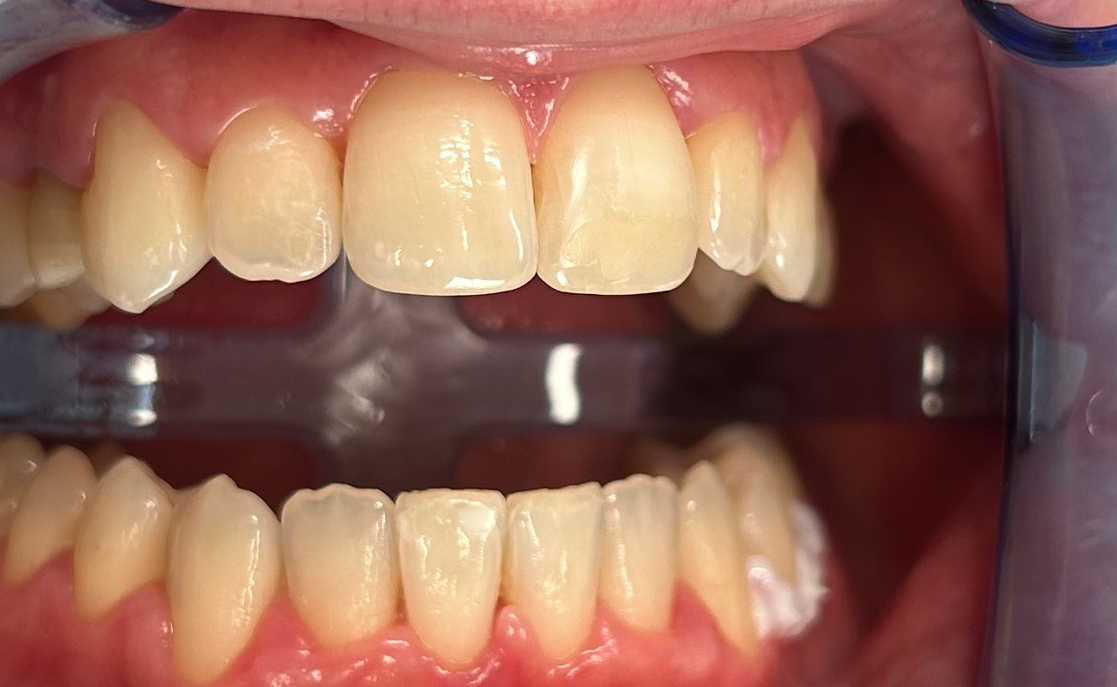

Poprawa estetyki uśmiechu: wybielanie zębów.

Usuwanie osadów i polerowanie dla zdrowego uśmiechu.

Profilaktyka i estetyka: usuwanie kamienia i wybielanie.